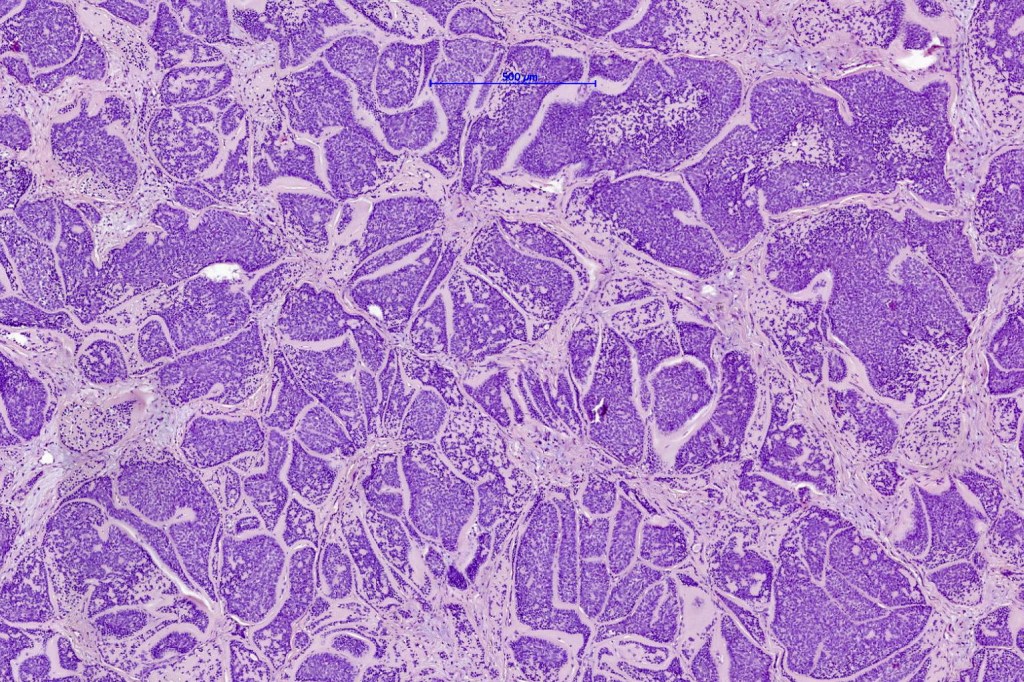

Histological features

•Dermal based

•Jigsaw/mosaic pattern arrangement of variably sized lobules of tumor cells with surrounding think, eosinophilic hyaline basement membrane

•Intralobular hyaline basement membrane material droplets

•Outer layer of intensely basophilic small cells surrounding larger central cells with pale staining or eosinophilic cytoplasm & vesicular nuclei

•Ductal differentiation